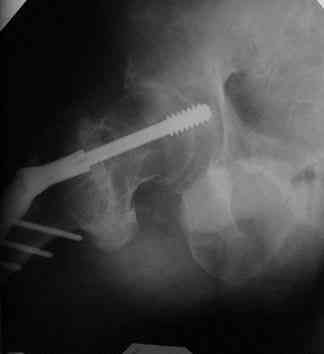

Все-таки хочу поделиться раз затронулась тема, может кому-нибудь и сгодиться. Это пример из области скорее трудноудаляемой. Пациент 50 лет, травма (низкоэнергетическая) 1,5 года назад. Оперирован через неделю (винт отечественный). Через 4 месяца выполнен контрольный снимок, сразу же возник вопрос: почему винт не телескопировался? Вопрос в общем-то так и остался без ответа.

При удалении (наркоз) после неимоверных усилий пришлось выкрутить фиксатор единым блоком и только тут все встало на свои места. См. фото.

Грустно+ Вот какие сюрпризы преподносят иногда коллеги.